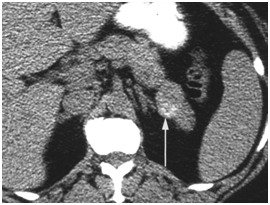

CT scan

CT scan has many advantages since it can be easily performed, is non-invasive and the images are easily interpretable for the surgeon. Insulinoma typically appear as well-defined, rounded, homogeneously masses of the pancreas. Because the majority of insulinoma are usually smaller than 2cm, dynamic CT scan should be performed; the sensitivity of the dynamic CT scan in the detection of insulinoma ranges from 30% to 66%. Dual-phase contrast spiral CT scan is more sensitive than other noninvasive imaging studies. In a group of seven patients with tumors that were biochemically proven but not previously located by ultrasonography, CT scan, or magnetic resonance imaging, six of seven tumors ranging from 6 to 18 mm were detected by dual-phase spiral CT scan. Atypical CT scan imaging of insulinoma includes hypoattenuating masses on enhanced CT or intra-arterial dynamic CT, cystic masses, and calcified masses (Figure 1–3).26–30

Figure 1 Insulinoma in an 87-year-old man with intractable hypoglycemia. Dual phase CT scan through the pancreas demonstrates a subtle, well-defined 1-cm enhancing lesion (arrow) in the pancreatic neck. A small cyst is also seen. A well-differentiated 1.2-cm ICT was completely excised at surgery. Histologic stains were positive for insulin. The hypoglycemia resolved after surgery. 23

Figure 2 Pancreatic insulinoma. Axial contrast-enhanced CT scan obtained during the arterial phase shows a homogeneous enhancing lesion (black arrow) in the uncinate process of the pancreas, just posterior to the superior mesenteric vein (white arrow). 24